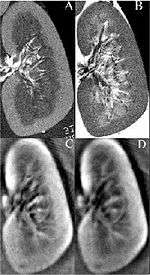

Thermoacoustic imaging was originally proposed by Theodore Bowen in 1981 as a strategy for studying the absorption properties of human tissue using virtually any kind of electromagnetic radiation.[1] But Alexander Graham Bell first reported the physical principle upon which thermoacoustic imaging is based a century earlier.[2] He observed that audible sound could be created by illuminating an intermittent beam of sunlight onto a rubber sheet. Shortly after Bowen's work was published, other researchers proposed methodology for thermoacoustic imaging using microwaves.[3] In 1994 researchers used an infrared laser to produce the first thermoacoustic images of near-infrared optical absorption in a tissue-mimicking phantom, albeit in two dimensions (2D).[4] In 1995 other researchers formulated a general reconstruction algorithm by which 2D thermoacoustic images could be computed from their "projections," i.e. thermoacoustic computed tomography (TCT).[5] By 1998 researchers at Indiana University Medical Center extended TCT to 3D and employed pulsed microwaves to produce the first fully three-dimensional (3D) thermoacoustic images of biologic tissue [an excised lamb kidney (Fig. 1)].[6] The following year they created the first fully 3D thermoaocustic images of cancer in the human breast, again using pulsed microwaves (Fig. 2).[7] Since that time, thermoacoustic imaging has gained widespread popularity in research institutions worldwide.[8] As of 2008, three companies were developing commercial thermoacoustic imaging systems - Seno Medical, Endra, Inc. and OptoSonics, Inc.

- ↑ Kruger RA, Kopecky KK, Aisen AM, Reinecke DR, Kruger GA, Kiser Jr W. Thermoacoustic computed tomography – a new medical imaging paradigm Radiology 1999,211:275-278.